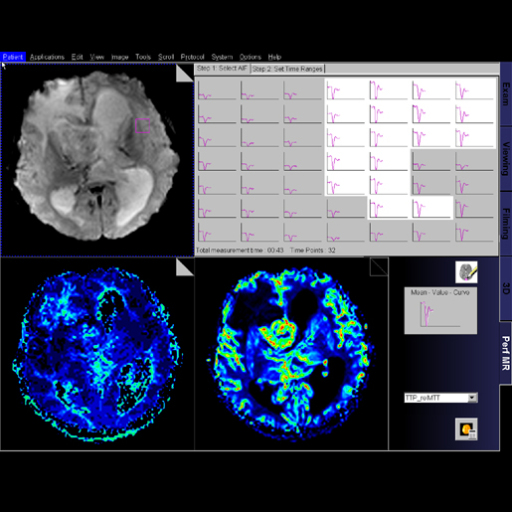

- Syngo BOLD Evaluation:

package for Inline BOLD imaging. Features This package provides statistical map calculations from BOLD

datasets and enables the visualization of task-related areas

of activation with 2D anatomical data. This allows the

visualization of the spatial relation of eloquent cortices

with cortical landmarks or brain lesions Additionally, evolving signal time courses in task-related

areas of activation can be displayed and monitored Functional and anatomical image data can be exported for

surgical planning as DICOM datasets, additionally all color

fused images and results can be stored or printed Statistical map generation: paradigm definition, calculation

of t-test maps 2D Visualization: fused display of fMRI results, color

t-test maps on anatomical datasets Inline real time monitoring of the fMRI acquisition Clinical Applications Neurosurgical planning Assess the effects of neurodegenerative diseases, trauma or

stroke on brain function Brain mapping

BOLD evaluation task card |